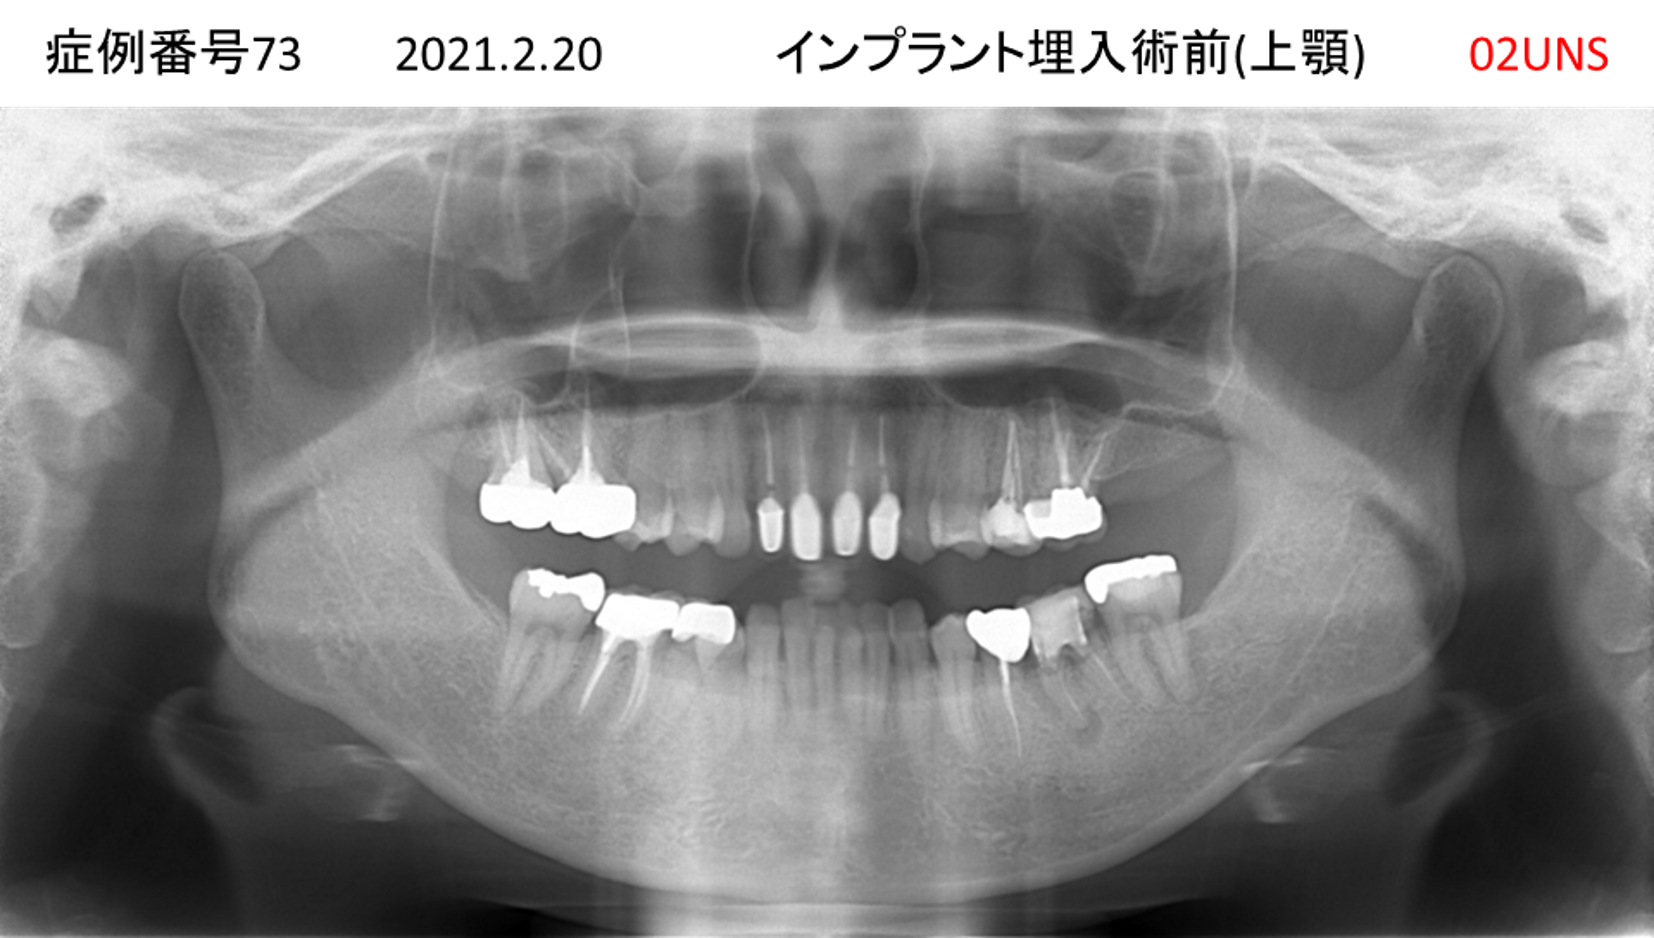

上の前歯が揺れてきてかめない患者様のインプラント症例

| 治療名称 |

インプラント |

| 治療費用 |

335万円+税 |

| 治療期間 |

4か月 |

| 患者さんの症状(主訴) |

上の前歯が揺れてきて噛めない |

| 治療内容 |

サイナスリフト 抜歯即時インプラント |

| 治療結果 |

ちゃんと噛めるようになった。不安がなくなった。見た目がとても良くなったのすごくうれしい。 |

| 治療の注意点(リスク/副作用) |

インプラントが壊れたら再治療が必要 |